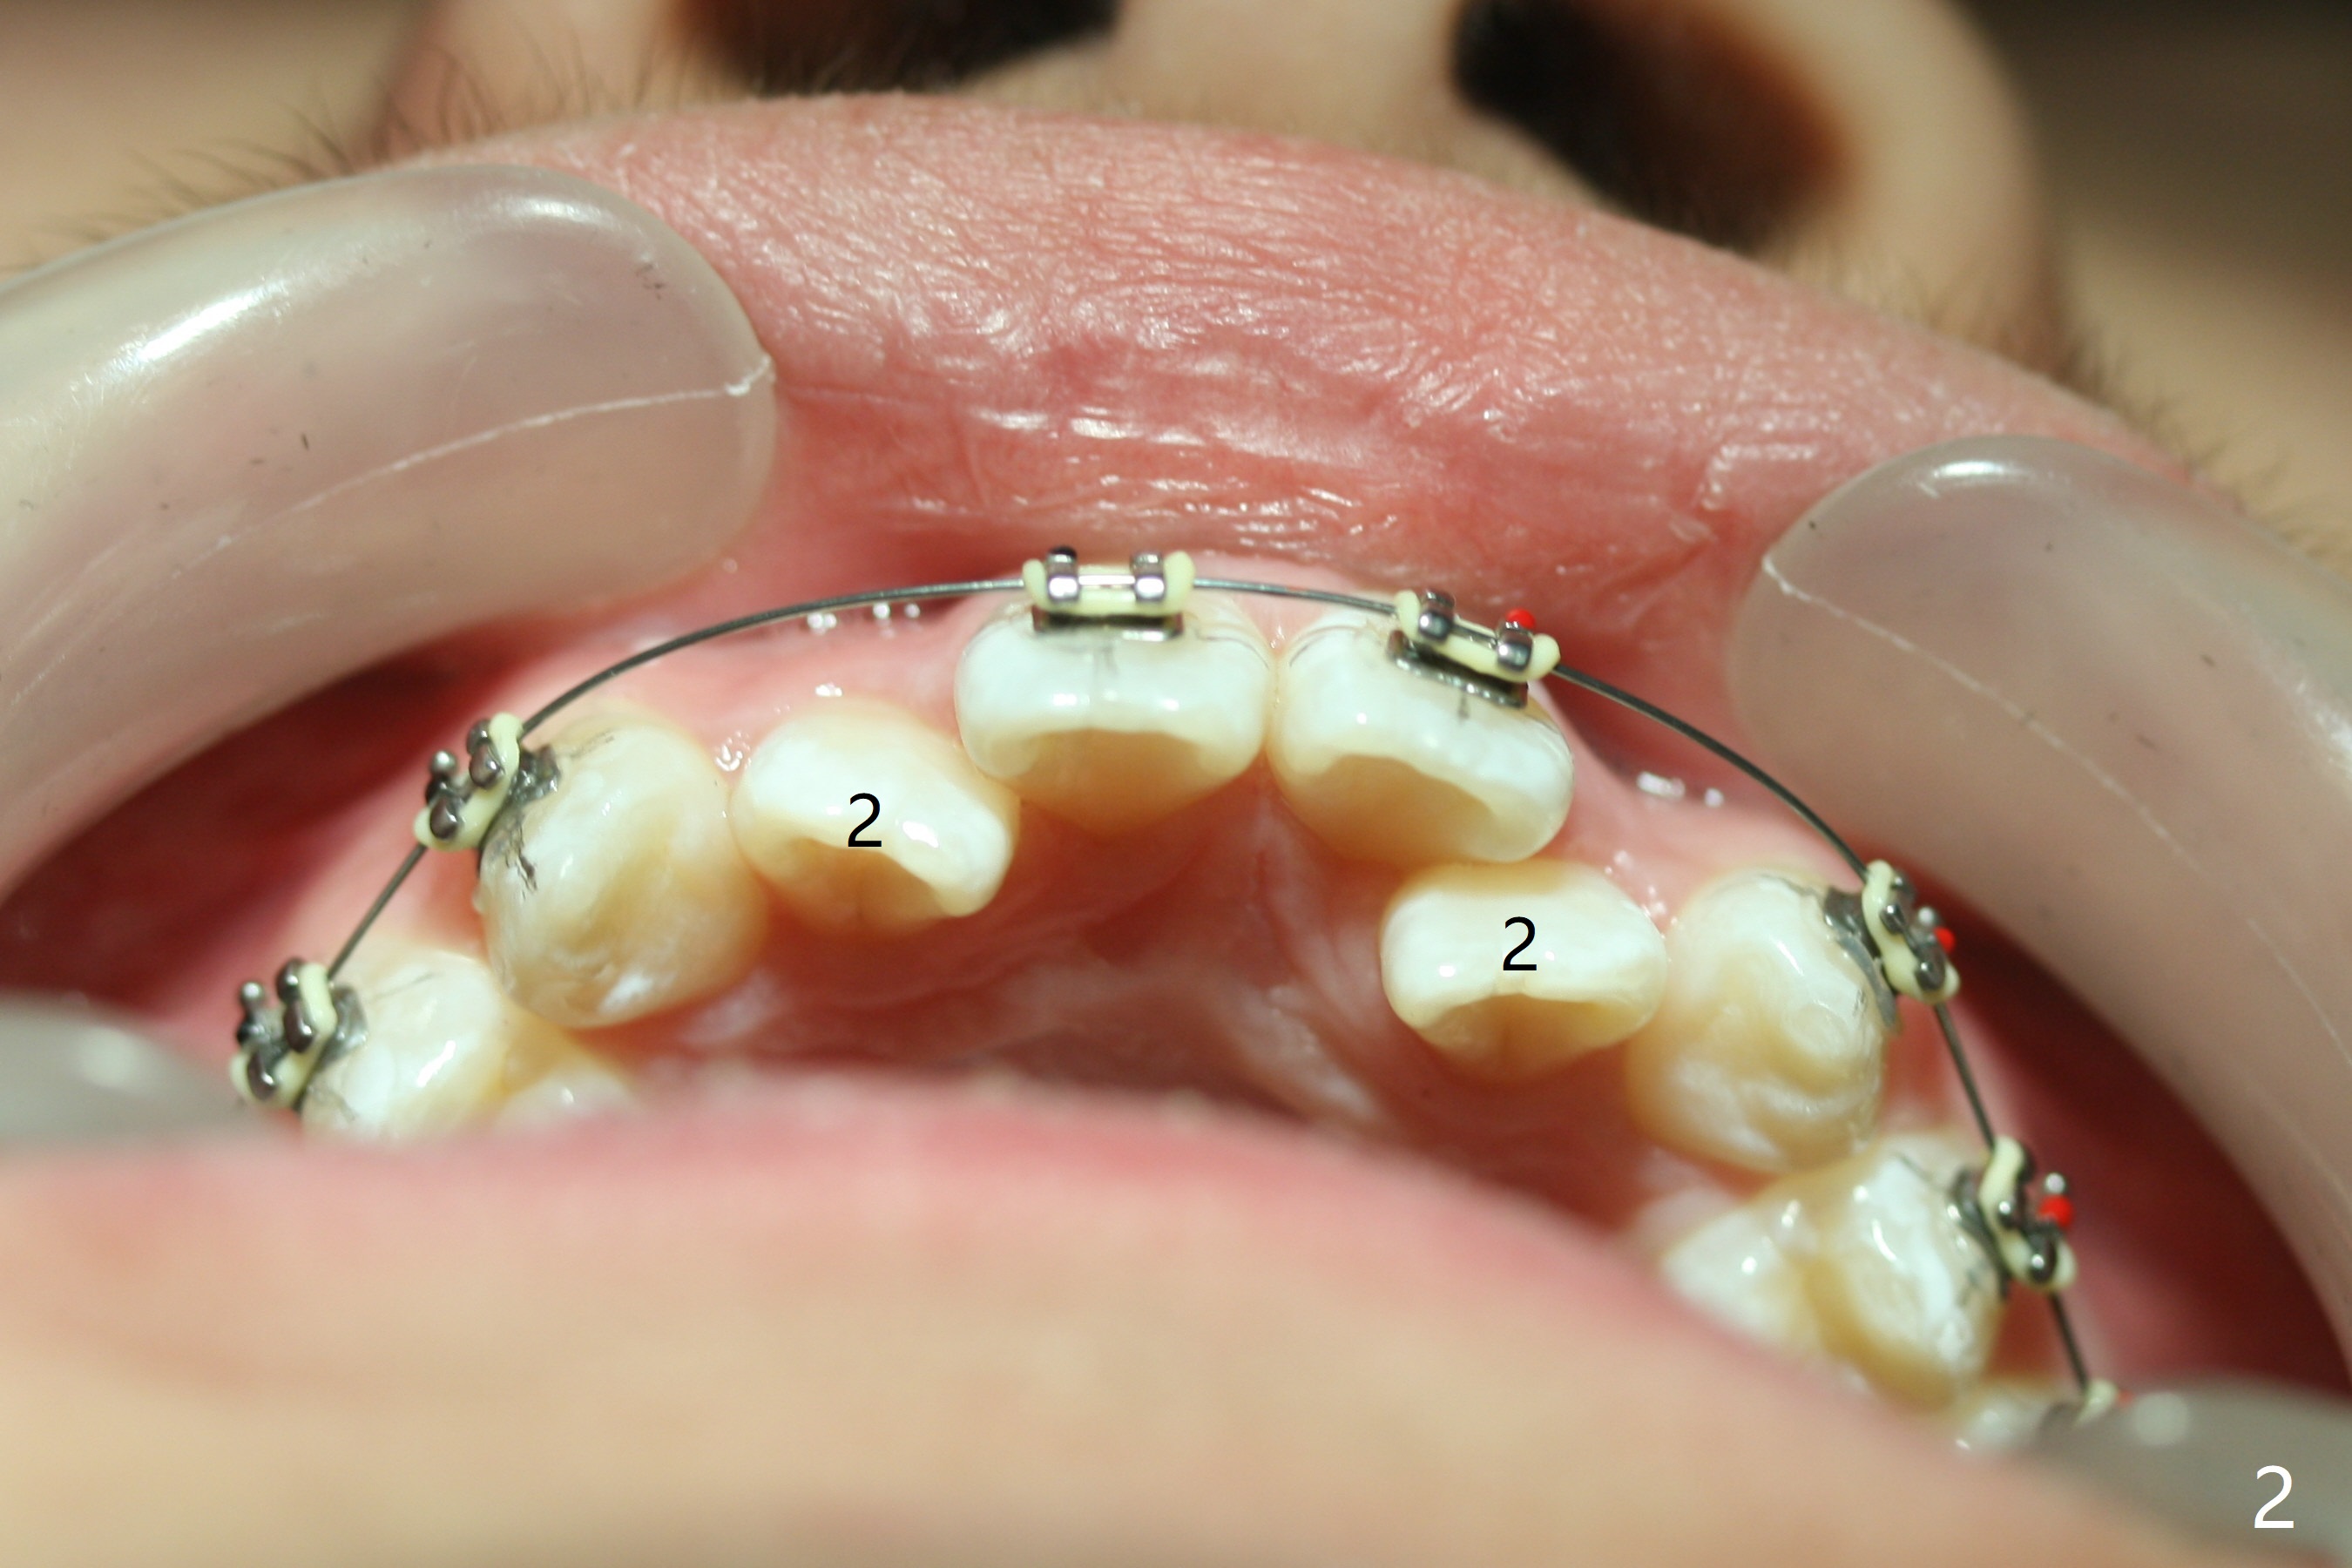

Cephalometric analysis shows Class III skeletal relationship. The roots of the upper anterior teeth (Fig.1,3 *) are prominent before treatment. In order to correct the cross bite of U2s (Fig.2,5), the upper arch needs expansion (Fig.4). Will the arch expansion cause buccal plate loss of the upper teeth? The upper dental midline matches the lower one by using the left open coil spring only (4 months 10 days post banding, Fig.6).